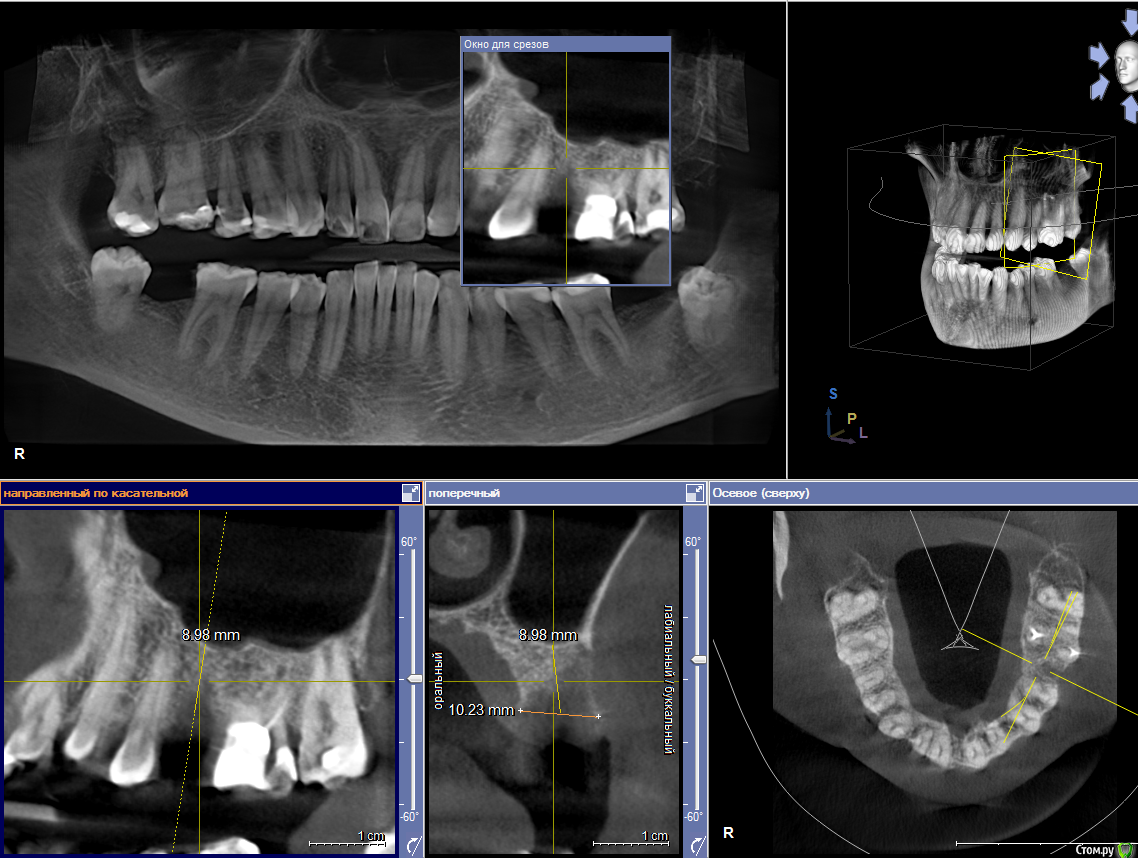

Amigo43 Опубликовано 3 сентября, 2019 Поделиться Опубликовано 3 сентября, 2019 Правильно ли я понимаю, что это штрауманн тл утопленный полированной шейкой в кость? Ссылка на комментарий

Dmitry DK Опубликовано 3 сентября, 2019 Автор Поделиться Опубликовано 3 сентября, 2019 Правильно ли я понимаю, что это штрауманн тл утопленный полированной шейкой в кость?да, это он Ссылка на комментарий

Dmitry DK Опубликовано 4 сентября, 2019 Автор Поделиться Опубликовано 4 сентября, 2019 так нужно было его просто глубже поставитьБыли такие мысли)Имплантат упёрся в нижнюю стенку синус. Весь винт с полированной частью 9,8 мм, шероховатая часть - 8 мм, от небной стеньки до синуса - 8 мм. Выбор был 1) закрытый синус, глубже платформа 2) выше платформа, без синусаВторой вариант выбран только по причине низких эстетических требований пациентки. 1 Ссылка на комментарий